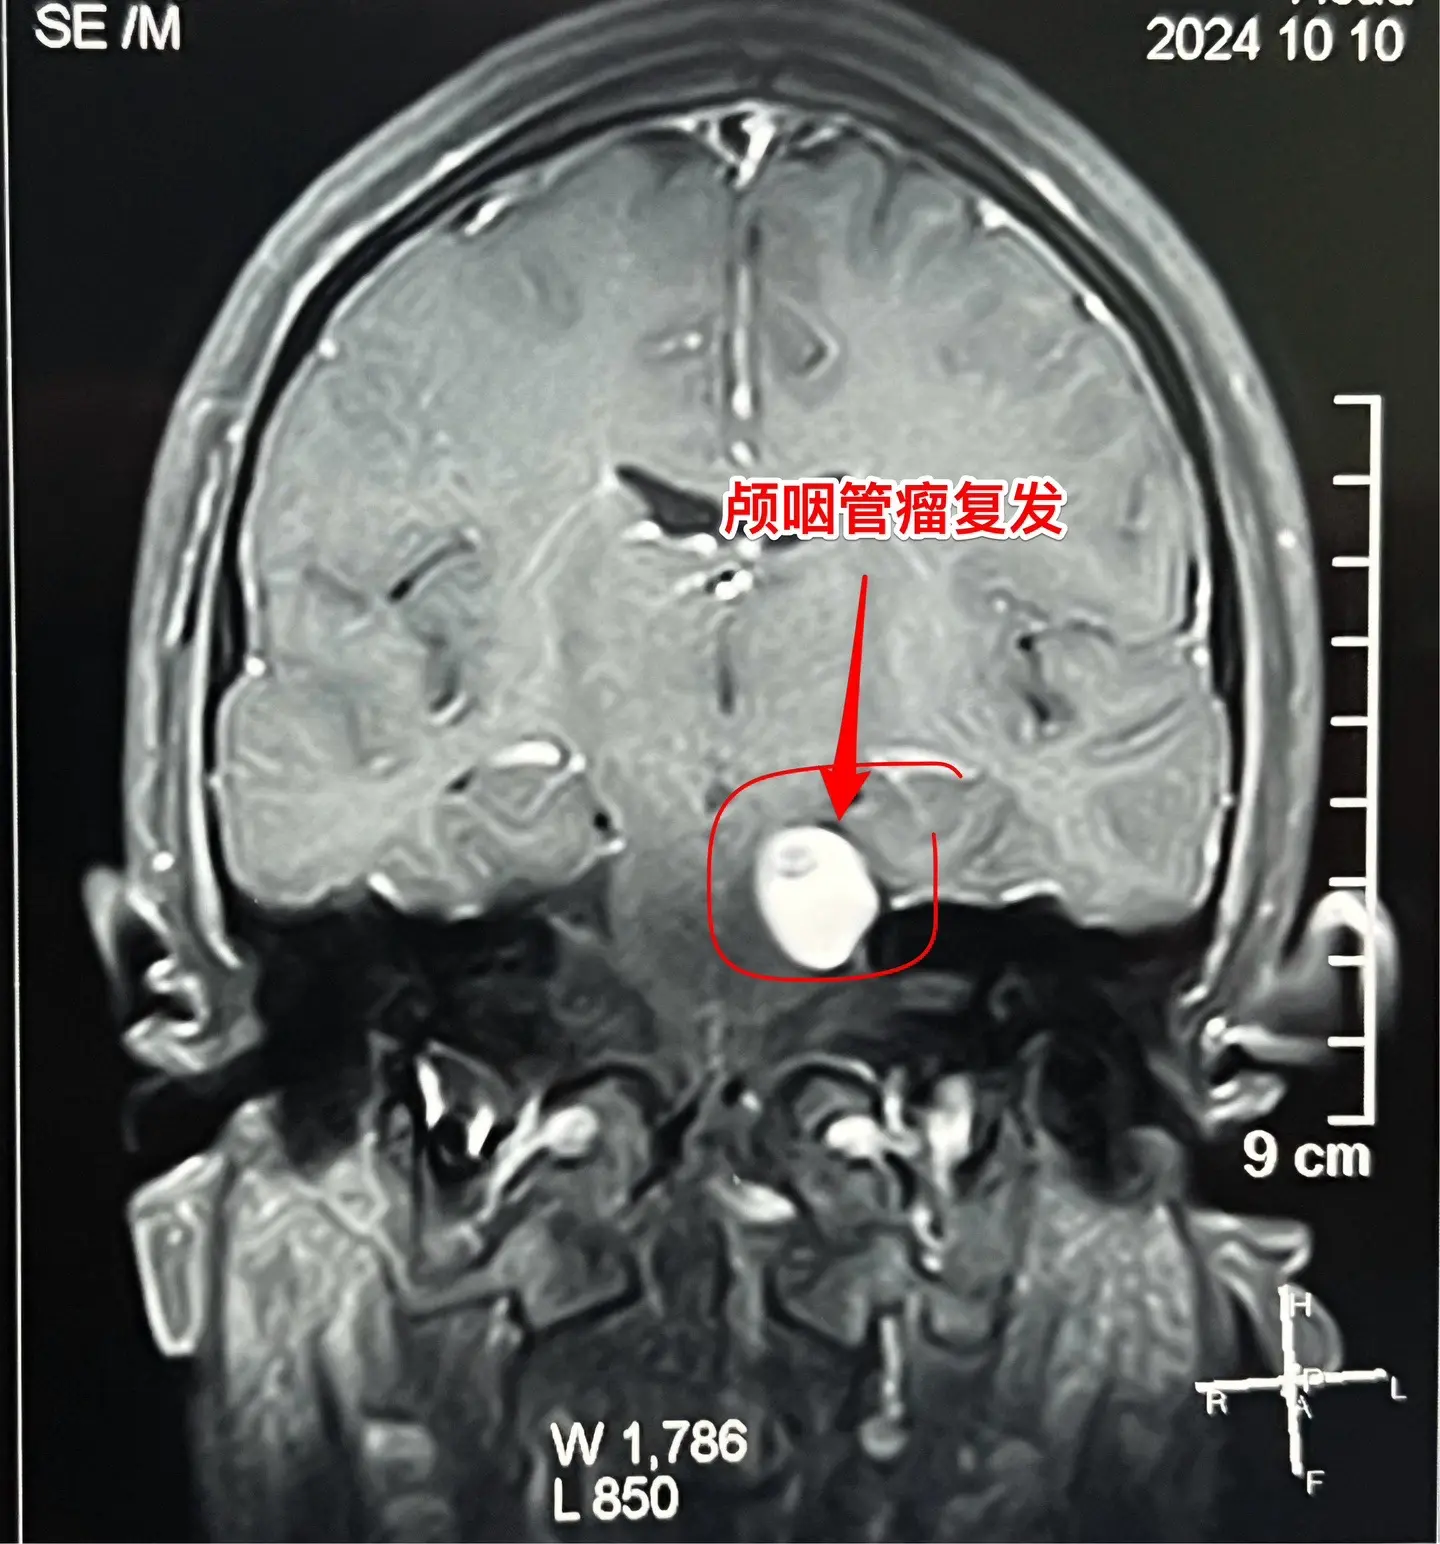

3次复发的颅咽管瘤也要积极治疗。16岁杭州女生,因颅咽管瘤于10年前在外院行开颅手术。8年前发现颅咽管瘤复发(在右侧额叶-鞍区)在我科作了手术,随后多年复查磁共振,7年内均未见肿瘤复发。本以为她的颅咽管瘤已经得到治愈,不曾想八个月前行磁共振检查发现肿瘤有复发迹象,体积很小,观察八个月常规复查磁共振发现肿瘤体积增大了许多,见图,肿瘤起源于左侧桥脑-中脑表面,和普通的颅咽管瘤位置不同。 10月11日作了手术,将这个复发肿瘤彻底切除了。手术后女孩子恢复很顺利,希望经过三次手术后肿瘤不再复发。